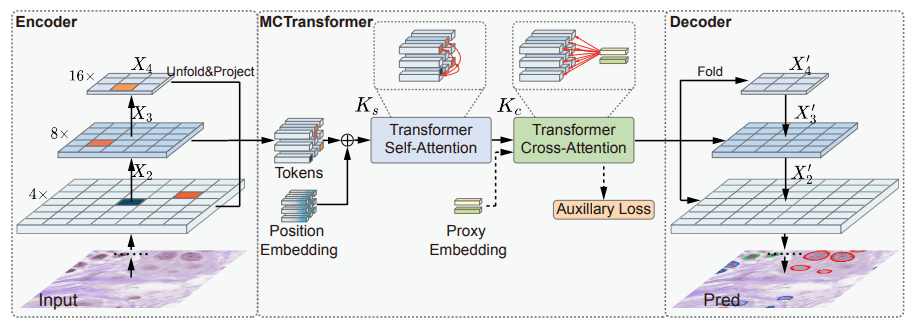

《Multi-Compound Transformer for Accurate Biomedical Image Segmentation》